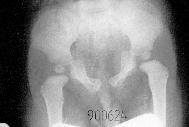

Description of X-ray pictures of pelvis. Asymmetry of shape of

pelvis, shifting in "symphysis of pubis", oblique position of os sacrum, wedge

deformity of L-4, L-5. Here in bottom of spine (in pelvis) scoliosis begins to

develop. This is confirmation of biomechanical influences of development of

scoliosis and connection with "standing" and "gait"(!)

Pictures of pelvis: oblique position of

pelvis as typical sign of "syndrome of contractures". This is caused by

"adductor muscles and soft tissue shortening of left hip" and "abductor muscles

and soft tissue shortening of right hip". Such X-ray picture in infants or

small children suggests / orders "the examination of spine in age of 3-4-5

years" to search / to look for scoliosis (!).